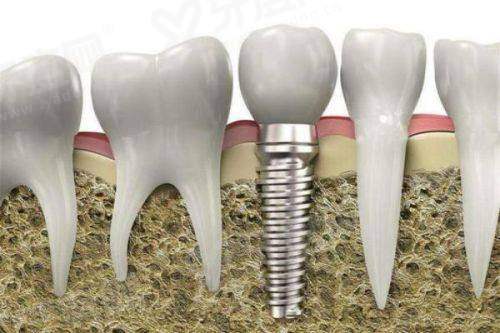

1、北京美莱口腔医院引进了数字化种植技术,通过CBCT三维立体成像,能精细获取患者口腔数据,然后制定个性化的种植方案,种植过程中使用种植导板,提高了种植的精细度和成功几率,减少了手术创伤。

3、北京美莱口腔对于牙齿修复项目,医院采用3D打印技术制作牙冠和种植体基台,不仅缩短了修复时间,还能确保修复体与口腔的贴合度,让修复后的牙齿更自然、更耐用。